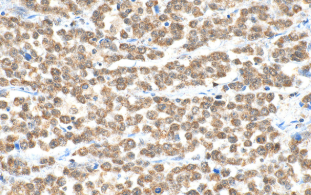

Immunohistochemical analysis of paraffin-embedded human colon cancer tissue slide using (ADAR1 antibody) at dilution of 1:200 (under 10x lens). Heat mediated antigen retrieval with Tris-EDTA buffer (pH 9.0)

Immunohistochemical analysis of paraffin-embedded human colon cancer tissue slide using (ADAR1 antibody) at dilution of 1:200 (under 40x lens). Heat mediated antigen retrieval with Tris-EDTA buffer (pH 9.0)